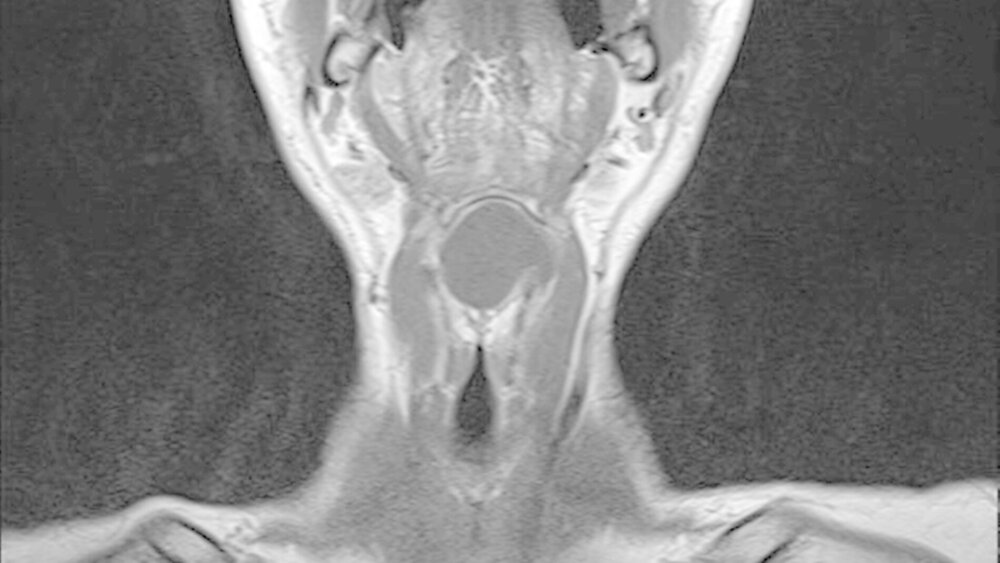

Die unter ambulanten Bedingungen angefertigte schnittbildgebende MRT-Untersuchung des Halses zeigte eine 41x35x27 mm große, gut abgrenzbare, und abgekapselte Raumforderung mit homogener Binnenstruktur. Die Dichtewertemessung wies anhand der Verteilung der Hounsfield-Einheiten einen mit flüssigkeits-äquivalentem, gefüllten Hohlraum auf (Abbildung 2a). Dieser war mit einer mittigen Einschnürung in der Medianebene des Halses und in der Mitte des Os hyoideum lokalisiert (Abbildung 2b). Dabei wird die Verdrängung des aerodigistiven, benachbarten Raumes sowie die Anhebung des Mundbodens und der Zungengrundmuskulatur deutlich (Abbildung 2c).